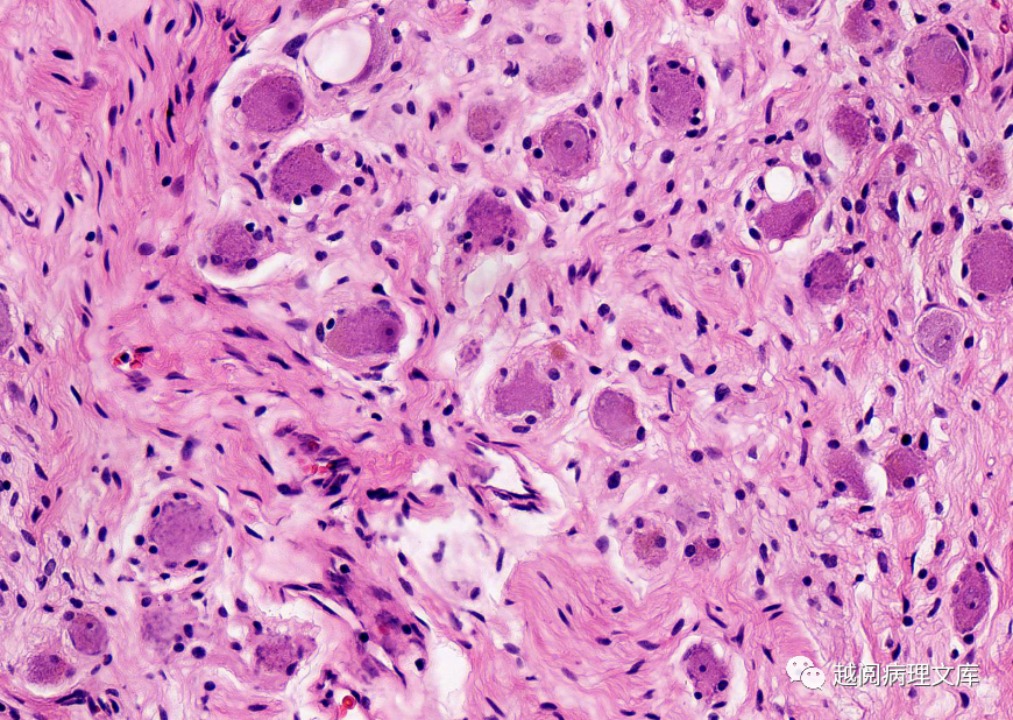

(3)节细胞的胞质丰富,呈淡嗜伊红色,核大,圆形或椭圆形,染色质淡,内含1~3个核仁。

2.病理特征

镜下其主要由大量的黏液基质和一些雪旺氏细胞、神经节细胞构成,由于大量黏液基质的存在,所以质地较柔软,沿周围组织器官间隙呈嵌入性生长,肿瘤较大时,邻近血管可被包埋或受压移位,但无狭窄、闭塞等受侵征象,很少有出血、坏死或囊变,部分可有斑点状、沙粒状钙化。